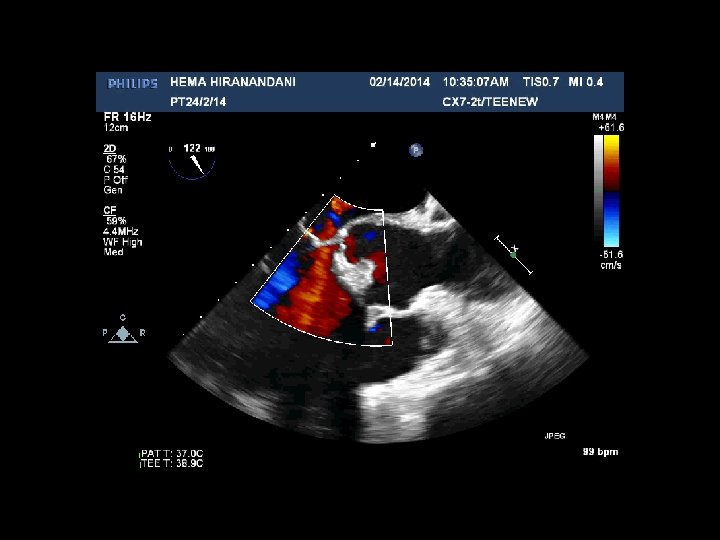

HEMA HIRANANDANI F 57 YRS • • • AVR BIO PROSTHETIC VALVE DEHISCENCE IE MULTIPLE VEGETATIONS ON BIO PRO VALVE AO ROOT ABSCESS SEVERE PARAVALVULAR AR RVSP= 37 mmhg

Hema Hirandani